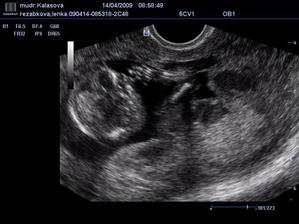

*****3.3.2009 nás čeká první poradna -------> První návštěva u nové dr. dopadla báječně.Viděla jsem miminko, i jeho srdíčko,které blikalo jako o závod.Měříme 7,4 mm.***** Další poradna 20.3.2008***** 5.3 mě začali trápit těhu nevolnosti.Brrrr,nikomu to nepřeju.*****10 tt (19.3.2009) - pomalinku začínáme nakupovat výbavičku,aukce jsou docela adrenalinovej sport 🙂)))*****20.3.2009 - Kontrola u dr,Utz,máme 3,03 cm,takže upraveno stáří těhotenství na 9+6 tt,ne 9+2 tt. Na UTZ jsem nádherně viděla mimiškovo ručičky i nožičky.Paní doktorka mi dokonce celý UTZ nahrála na flasch kartu,takže na mimíse můžu koukat i doma.Dostala jsem těhu průkajdu a cestou domů jsem zase mimísovi za odměnu něco koupila.***Oznámeno rodině maminky.Tatínkovo rodina se to dozví cca 30.3.09.-*****30.3.2009 Dnes přišla na návštěvu miláčkovo maminka.A jelikož měla 20.3. narozeniny pojali jsme velké oznamování jako dárek.Koupily jsme lahvinku červeného,kyti a přáníčko.Do obálky za přáníčko jsme nastražily řidičák na kočárek a fotečku z UTZ.Když jsem jí předávala přáníčko,řekla jsem jí,aby se na to raději posadila.A jak mamča vytahovala přáníčko vypadl na ní ten řidičák.Na něj koukla:´´Hm,řidičák na kočárek????????´´Pak koukla na nás.´´To jako,že čekáte ????????´´ a já se jen uculila,na nic jinýho jsem se nezmohla.No a nastávající babička na to´´No ještě,že jsem si na to sedla´´*****6.4.2009 - Koupen kočárek (Naštěstí nejsme pověrčivý a tak výhodná koupě by se už nemusela objevit.),vanička a polohovací lehátko.*****Třetí poradna ---- 14.4.2009 - Tlak máme v pořádku,na váze jsem se trochu zděsila 59,5 kg,tj. +7 kg,ale paní doktorka nic neříkala.Při UTZ jsem si poplakala viděla jsem ručičky ,nožičky,5 prstíků,nosní kůstku.

CRL je 6,88 cm,tj. 13+1 tt ---

FL je 0,9 cm,tj. 12+5 tt (délka stehenní kosti) ---

BPD je 2,2 cm,tj. 13+6 tt (Hlavička od ucha k uchu).Prý máme přímo ukázkový miminko.Jsem ale absolutně zmatená,jak je to naše štěstíčko vlastně starý.*****6.5.09 - Dnes jsem byla u dr zase na kontrole,tentokrát šla se mnou dcerka.Tlak super,váha 61,5 kg,takže ofiko 9 kg nahoře.Na dnešní kontrolu UTZ v plánu nebylo,ale když se přišla podívat starší sestra,tak jí paní doktorka miminko ukázala.Ručičky,nožičky,tělíčko a hlavičku a malá byla spokojená jako blecha.I z tohoto kratičkého vyšetření máme fotečku.A dnes bylo UTZ poprvé přes bříško.Sestřičkám jsem darovala 3 zkumavky krve:Na Downův syndrom,rozštěpy a na mojí žádost i na toxoplazmozu,na výsledky si mám volat 15.května..Dostala jsem doporučení na internu,na genetický UTZ do NATALARTu.Další kontrola až 4.6,ach jo.A dnes jsem konečně objednala můj vysněnej přebalováček.*****Od 2.5.2009 - -16+3 tt - naše štěstíčko o sobě konečně začalo dávat vědět.Opírá se mi o bříško zevnitř,pohyby jako takové ještě necítím,ale tlačí mě někdy dost silně.Tlaky se objevují denně,takže jsem si jistá,že je to náš poklad.******13.května 2009 - Jsem nedočkavec,tak jsem už dneska zkusila zavolat na výsledky testů krve a výsledek?ČEKÁME ÚPLNĚ ZDRAVÉ MIMINKO,HURÁÁÁÁÁÁÁÁÁÁÁÁ****** 26.5.2009 - 19+6 tt Dnes mě naše miminko poctilo 1 pořádným kopancem,do dneška to bylo jen takové lechtání a tlaky na břišní stěnu.*****2.6.2009 - Dnes jsme byly na velkém UTZ,vážíme cca 370 g a čekáme zdravou HOLČIČKU.****4.6.09 - Další kontrola u dr.Váha 66 kg,tzn +13,5 kg.Jaterní testy i laboratoř v pořádku,tlak super.Jen mám bílkovinu v moči.*****16.6.2009 - Dnes jsem byla na testu na cukrovku.No a jak to dopadlo,tak moc mi to chutnalo,že jsem se pozvracela.Doktorka mě na to naštěstí znova nepožene.Je fakt zlatá.*****Další poradna 4.7.2009 - 25 tt **** 28.6.2009 - 24+1 tt - Dneska se naše malinká rozkopala tak,že si začínám myslet,že bude kopat za nároďák.Už to nejsou ty ojedinělé kopance,ale kope do mě třeba 2 hodiny v kuse.Někdy je to nepříjemné,ale aspoň o cácorce vím a už se tolik nestrachuju,jestli je v pořádku.*****Kontrola ve 25 tt -2.7.09 - Tak jsem sice dneska na kontrole sice dostala prenatal box,ale radost z toho vůbec nemám.Mám asi nejspíš zánět močáku,protože mám nějakou potvoru v moči,takže se mám prolejvat urologickým čajem.